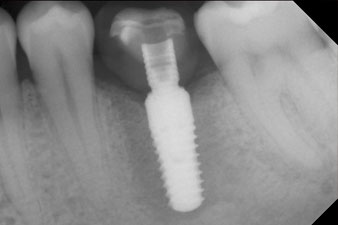

After healing of the soft tissue, the implant stability was measured again before delivery of the prosthetic restoration.

Both values were virtually unchanged and were between the medium and the high range – where the lower value is always used as the reference value that determines the treatment.

Therefore, successful osseointegration and adequate biological stability could be recorded, which enabled an impression to be taken in the same session.

The final pictures show the screw-retained monolithic composite crown in place and the x-ray check (Fig. 9 and 10) (6).

x-ray check

Fig. 10: The x-ray check shows the success of the osseointegration and the crown screwed in position without a gap.